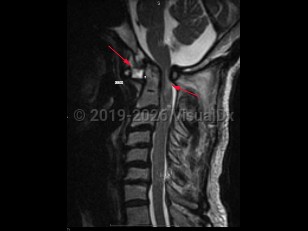

Atlantoaxial instability (AAI) is defined as excessive motion between the first cervical vertebra, the atlas, and the second cervical vertebra, the axis. The atlantoaxial segment is an anatomically complex section of the spinal column, composed of unique bones, articulations, and ligaments, with critical neurovascular structures intimately involved. The atlantoaxial segment is responsible for significant motion in the spine, and, in fact, is responsible for over half the possible axial rotation of the cervical spine. Disruptions of any of the ligaments or articular processes that afford nonpathologic motion of the atlantoaxial segment may result in instability of the complex. AAI can occur due to trauma, rheumatoid arthritis, congenital abnormalities (including up to 20% of Down syndrome patients), degenerative changes, head and neck infections, neoplasms, or iatrogenic etiologies. Most commonly, AAI results from compromise of the ligamentous complex; however, fractures or destructive processes affecting the osseous elements may also result in AAI.

AAI can occur in 3 directions: rotation, flexion-extension, and distraction leading to excessive displacement, which can result in subluxation or even dislocation.

Anterior atlantoaxial subluxations are more common in adults and result from any of the pathologies listed above. Anterior subluxations result in neurologic deficits or death in one-third of patients. Patients with rheumatoid arthritis (RA) are at most risk for dislocation in the anteroposterior (AP) plane but can develop rotational AAI as well.

Posterior atlantoaxial subluxations are rare and often occur from erosion of the odontoid process of the axis.